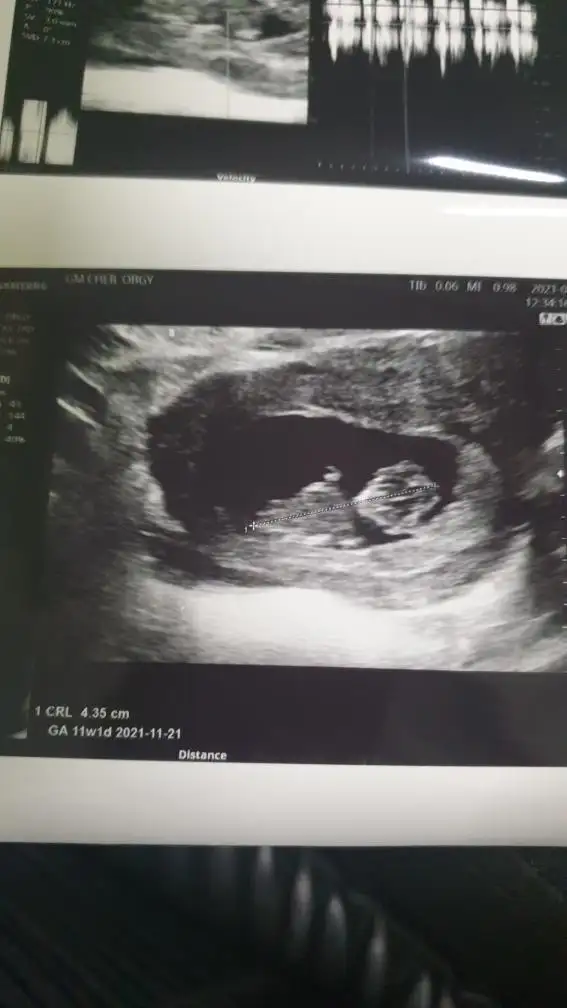

Canım Ikra meyra bu ultrasona da bakar mısın cok merak ediyoruz bi yakınımızın 12.haftada

• 0348DA3E-1526-4C95-845A-A221E6980DCA.webp

19,2 KB · Görüntüleme: 60